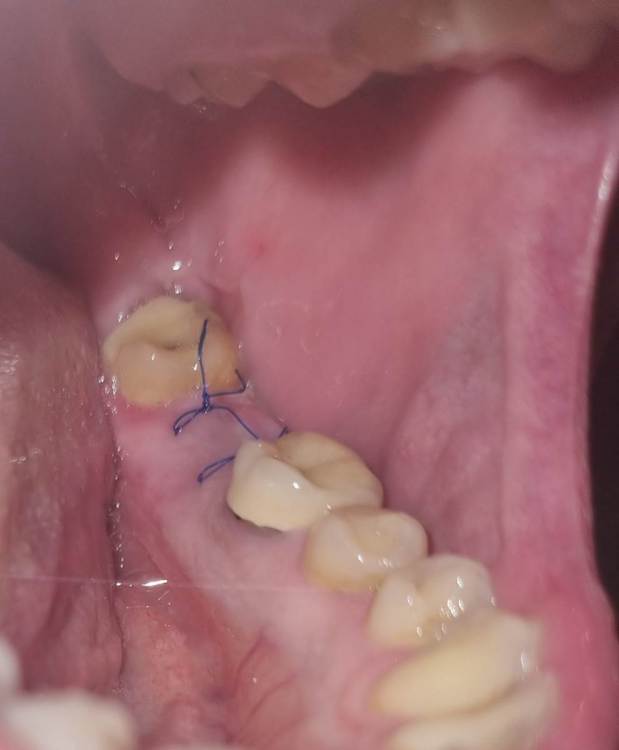

Chelovek2012 Опубликовано 6 декабря, 2023 Автор Поделиться Опубликовано 6 декабря, 2023 (изменено) Скажите, это ОК, или нужно идты к стоматологу снова и подшивать десной? Не болит, температуры нету. Изменено 6 декабря, 2023 пользователем Chelovek2012 Ссылка на комментарий

Irouil Опубликовано 7 декабря, 2023 Поделиться Опубликовано 7 декабря, 2023 Судя по рентген снимку у Вас установлен формирователь десны, если это действительно так - все ок 1 Ссылка на комментарий

Chelovek2012 Опубликовано 7 декабря, 2023 Автор Поделиться Опубликовано 7 декабря, 2023 Если чесно, я не знаю, что это. Я приходил на установку ипланта. 2,5 недели назад мне вставили это вместе с имплантом и сказали придти через 3 месяца. Ссылка на комментарий

АнтонТЛТ Опубликовано 7 декабря, 2023 Поделиться Опубликовано 7 декабря, 2023 Формирователь десны вкручен, перед протезированием его поменяют на широкий 1 1 Ссылка на комментарий

Chelovek2012 Опубликовано 10 декабря, 2023 Автор Поделиться Опубликовано 10 декабря, 2023 07.12.2023 в 14:26, АнтонТЛТ сказал: Формирователь десны вкручен, перед протезированием его поменяют на широкий То есть, нормально, что его видно? Я думал, что вся конструкция будет покрыта десной Ссылка на комментарий

АнтонТЛТ Опубликовано 10 декабря, 2023 Поделиться Опубликовано 10 декабря, 2023 Он должен быть виден, но иногда десну натягивают на него преследуя определенные цели. 1 Ссылка на комментарий

red_butler Опубликовано 11 декабря, 2023 Поделиться Опубликовано 11 декабря, 2023 18 часов назад, Chelovek2012 сказал: То есть, нормально, что его видно? Я думал, что вся конструкция будет покрыта десной это один из вариантов установки формирователя десны Ссылка на комментарий